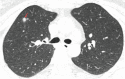

A new type of coronavirus (2019-nCoV) is rapidly spreading worldwide and causes pneumonia, respiratory distress, thromboembolic events, and death. Chest computed tomography (CT) plays an essential role in the diagnosis of viral pneumonia, monitoring disease progression, determination of disease severity, and evaluating therapeutic efficacy. Chest CT can show important clues of 2019-nCoV disease (also known as COVID-19) in patients with an appropriate clinic. Prompt diagnosis of COVID-19 is essential to prevent disease transmission and provides close clinical observation of patients with clinically severe disease. Therefore, radiologists and clinicians should be familiar with the CT imaging findings of COVID-19 pneumonia. Herein, we aimed to review the imaging findings of COVID-19 pneumonia and examine the critical points to be considered for imaging in cases with COVID-19 suspicion.